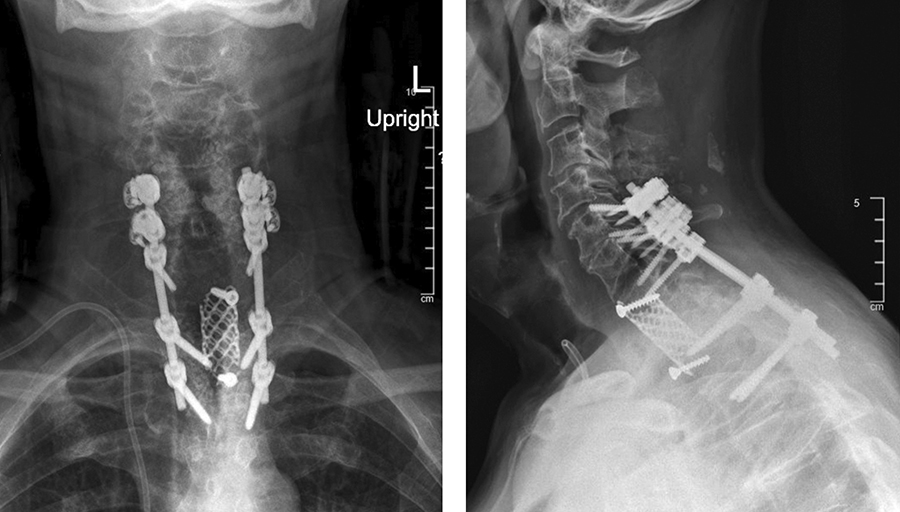

· C5-T3 posterior instrumentation with the DePuy Synthes SYMPHONY OCT System. Given the patient’s suboptimal bone quality, C5 and C6 lateral mass screws were reinforced with two MULTIPOINT SECURE screws placed bilaterally for an additional eight screws (Fig 7).

The patient had immediate relief of the radicular symptoms postoperatively. Three months postoperatively (Fig 8), he had no neck pain and was anxious to return to daily exercise at the gym. He had maintained resolution of his radiculopathy and was satisfied with the outcome.